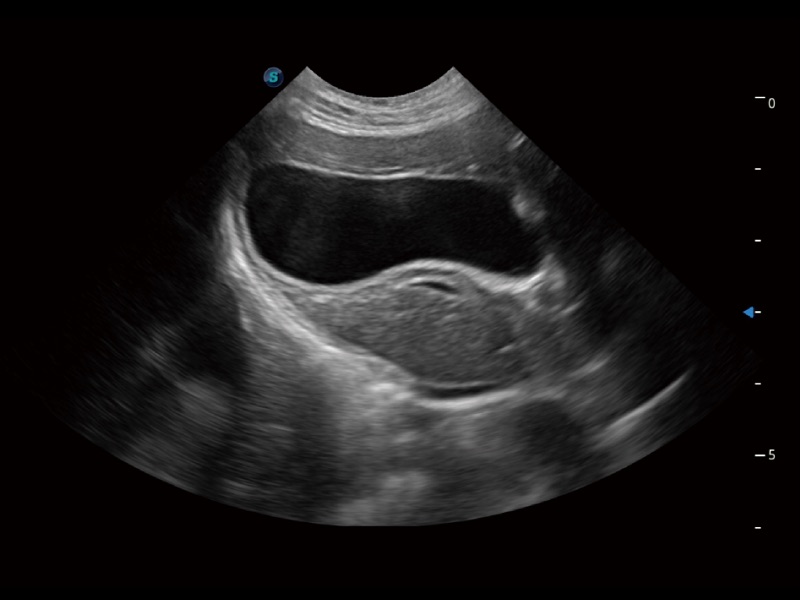

貓、中小型犬及小型異寵動(dòng)物

ProPet 70 進(jìn)一步提升了微米成像算法,更加注重對基礎(chǔ)原始圖像的還原和保留,在有效減少斑點(diǎn)噪聲、增強(qiáng)組織邊界顯示的同時(shí),避免過度優(yōu)化丟失真實(shí)的解剖信息。